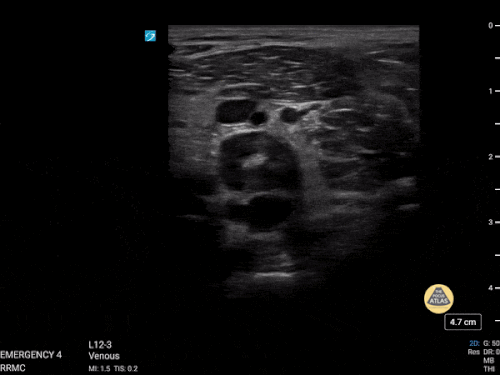

Patolojik DVT USG:

| Sol popliteal vende oklüziv DVT

|

Popliteal DVT

| DVT (Derin ven trombozu)

Büyük safen ven trombozu